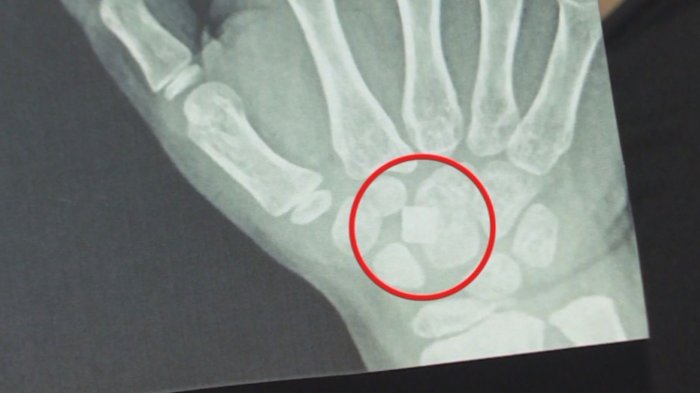

Denuncian negligencia médica: Niña vive hace tres meses con vidrio enterrado en su mano

Andrea Arriagada compartió la historia de su hija, María Josefina, quien tuvo un accidente hace tres meses y como resultado aún aloja un vidrio en su mano.